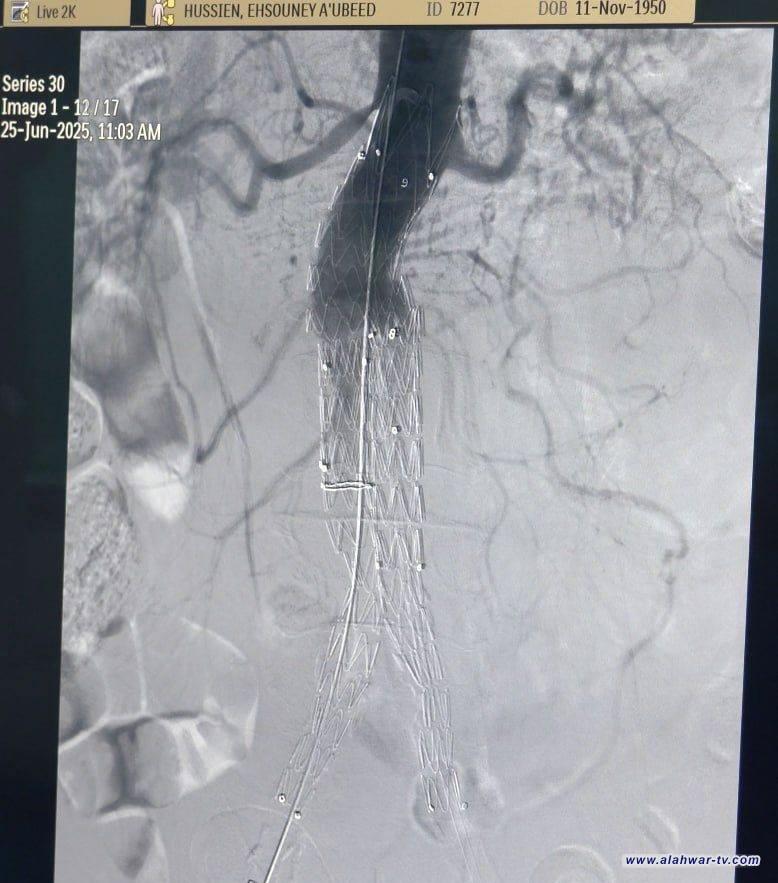

في إنجاز طبي متقدم يُسجَّل لأول مرة في محافظة ذي قار، تمكن فريق طبي متخصص في مستشفى الناصرية للقلب، وبالتعاون مع مركز النجف لجراحة القلب والتداخل القسطاري، من إجراء عملية نوعية دقيقة لإصلاح أم الدم الأبهرية (تمدد الشريان الأورطي البطني) باستخدام تقنية القسطرة، وبتخدير موضعي فقط، دون الحاجة إلى التخدير العام.

وذكر بيان لصحة ذي قار انه جرى هذا التدخل الجراحي لمريض كان يعاني من حالة صحية حرجة مصحوبة بآلام حادة في البطن، ما استدعى التدخل السريع والآمن باستخدام أحدث الأساليب الطبية لتقليل المخاطر والمضاعفات المحتملة، خاصة ما يرتبط منها بالتخدير العام.